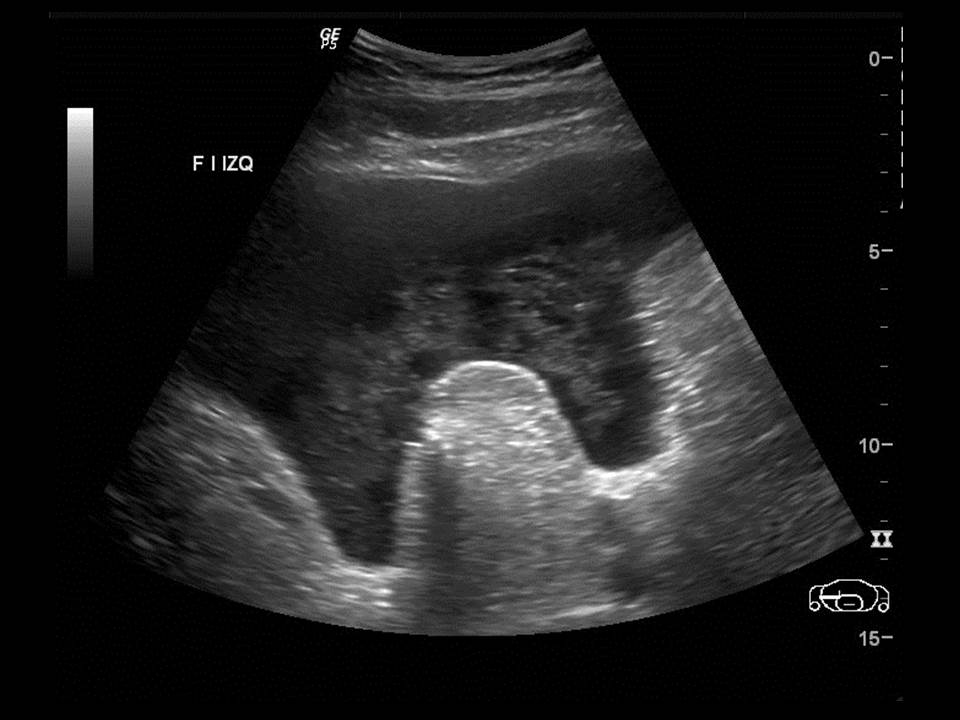

Paciente de 12 años con dolor abdominal. Remitida para estudio de masa intraabdominal.